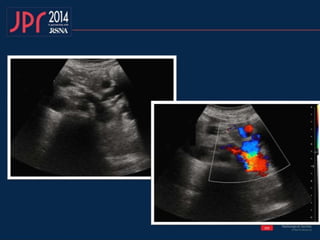

• Conteúdo patológico

– Transformação cavernomatosa

Veia Porta

Veia Porta • Conteúdopatológico – Trombose – Trombo tumoral – Transformação cavernomatosa